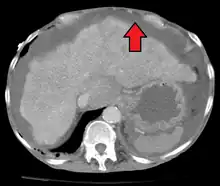

Liver cirrhosis with ascites

Ultrasound investigation is often done before attempts to remove fluid from the abdomen. This may reveal the size and shape of the abdominal organs, and Doppler studies may show the direction of flow in the portal vein, as well as detecting Budd–Chiari syndrome (thrombosis of the hepatic vein) and portal vein thrombosis. The sonographer also can estimate the amount of ascitic fluid, and difficult-to-drain ascites may be drained under ultrasound guidance. An abdominal CT scan is more accurate than a sonogram to reveal abdominal organ structure and morphology.[12]